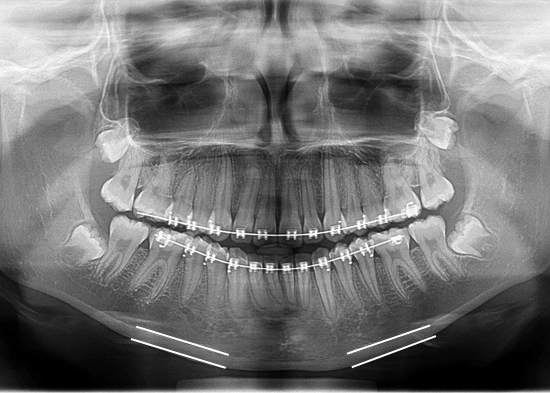

A través de la radiografía panorámica se puede evaluar el evaluar el Ancho Cortical Mandibular, específicamente en la región premolar inferior. Esta zona fue seleccionada porque presenta menor sobreproyección de estructuras radiografiadas y menor grado de magnificación, debido a que dicha región premolar se encuentra más cerca del plano o área focal durante la toma radiográfica.

El procedimiento consiste en identificar el foramen mentoniano, luego se trazar una línea paralela al cuerpo mandibular y posteriormente otra línea paralela a la línea del cuerpo mandibular, la cual determina en milímetros el Ancho Cortical Mandibular

En muchas ocasiones, al observar en una radiografía panorámica la cortical mandibular esta puede estar disminuida en su grosor, lo cual indica una disminución de la densidad mineral ósea a nivel de los maxilares del paciente y por ende, un signo de osteoporosis.